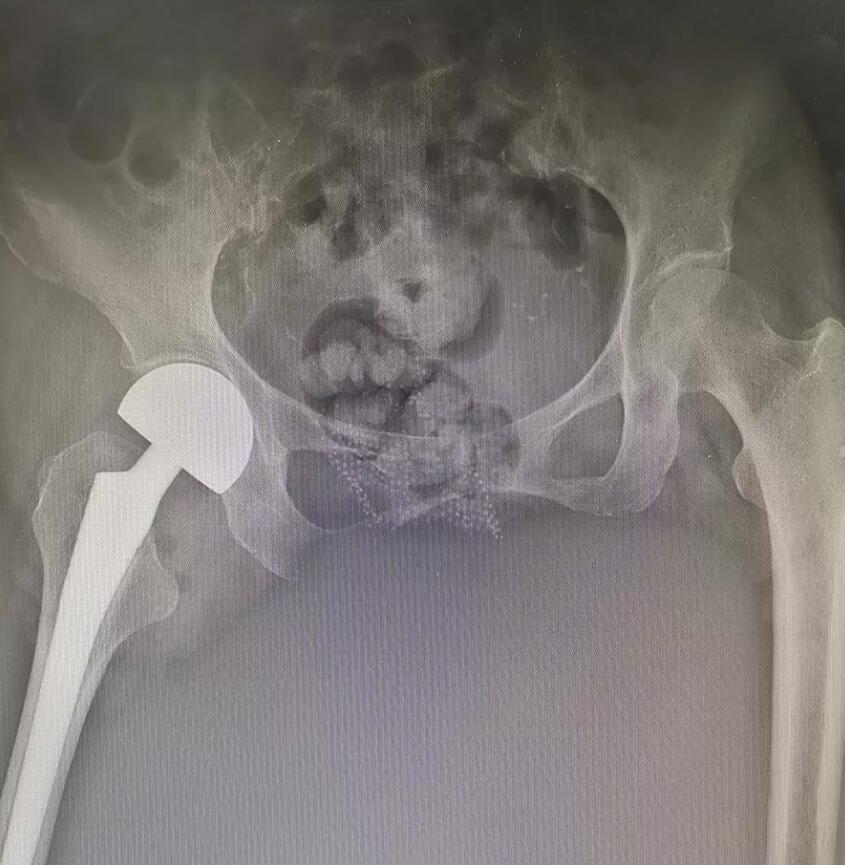

醫(yī)生在詳細(xì)了解了病人情況之后與醫(yī)院專(zhuān)家及醫(yī)護(hù)人員對(duì)病情進(jìn)行了深入研究,及時(shí)為患者制定了合理有效的治療方案。在與家屬溝通確定之后對(duì)患者進(jìn)行了半髖置換手術(shù),由于此患者的病情復(fù)雜,此手術(shù)風(fēng)險(xiǎn)比較大,手術(shù)難度也比較高。

然而就是在這種高難度、高復(fù)雜、高危險(xiǎn)的情況下,我院醫(yī)生依然順利地完成了半髖置換手術(shù)

經(jīng)過(guò)手術(shù)的治療和康復(fù)的練習(xí),患者已經(jīng)可以早期下床。